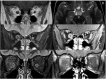

Relapsing demyelinating syndromes (RDS) in children encompass a diverse spectrum of entities including multiple sclerosis (MS) acute disseminated encephalomyelitis (ADEM), aquaporin-4 antibody associated neuromyelitis optica spectrum disorder (AQP4-NMOSD) and myelin oligodendrocyte glycoprotein antibody disease (MOG-AD). In addition to these, there are "antibody-negative" demyelinating syndromes which are yet to be fully characterized and defined. The paucity of specific biomarkers and overlap in clinical presentations makes the distinction between these disease entities difficult at initial presentation and, as such, there is a heavy reliance on magnetic resonance imaging (MRI) findings to satisfy the criteria for treatment initiation and optimization. Misdiagnosis is not uncommon and is usually related to the inaccurate application of criteria or failure to identify potential clinical and radiological mimics. It is also notable that there are instances where AQP4 and MOG antibody testing may be falsely negative during initial clinical episodes, further complicating the issue. This article illustrates the typical clinico-radiological phenotypes associated with the known pediatric RDS at presentation and describes the neuroimaging mimics of these using a pattern-based approach in the brain, optic nerves, and spinal cord. Practical guidance on key distinguishing features in the form of clinical and radiological red flags are incorporated. A subsection on clinical mimics with characteristic imaging patterns that assist in establishing alternative diagnoses is also included.